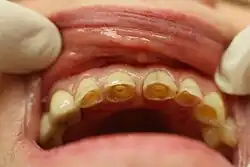

В отличие от физиологической стираемости зубов, патологическая стираемость характеризуется более ранней и значительно выраженной потерей твёрдых тканей, которая чаще носит генерализованный характер и отмечается на всех зубах. При патологической стираемости зубов наблюдается стирание эмали и дентина, доходя до шейки зубов, причем после обнажения дентина её стирание идет более интенсивно, так как дентин — более мягкая ткань. В результате этого по краям зуба образуются острые края эмали, которые часто травмируют слизистую оболочку щёк и губ. Если лечение вовремя не проводится, то стирание быстро прогрессирует и зуб становится значительно короче. В таких случаях наблюдаются признаки уменьшения нижней трети лица: складки у уголков рта, изменение височно-нижнечелюстного сустава, боль в области височно-нижнечелюстного сустава и языка, снижение слуха.

При начальных проявлениях патологической стираемости зубов появляется чувствительность к температурным раздражениям, а по мере углубления процесса появляются боли от химических и механических раздражений. По внешним клиническим проявлениям традиционно различают горизонтальный, вертикальный и смешанный тип стираемости зубов.[1]:72. При этом убыль тканей происходит либо в горизонтальной плоскости, тогда стираются режущие края зубов, бугры и жевательные поверхности, либо в вертикальной плоскости, и тогда убыль тканей происходит на вестибулярной поверхности зубов. Вертикальная стираемость зубов, как самостоятельная нозологическая единица, встречается крайне редко. Чаще она сочетается с горизонтальной стираемостью, что определяется как смешанный тип стираемости, а также и с другими формами некариозных поражений зубов (эрозиями, клиновидными дефектами). Существует несколько классификаций повышенной стираемости зубов, предложенных разными авторами, но наиболее широкое применение получила классификация М. И. Грошикова (1985), согласно которой выделяют три степени стираемости зубов в зависимости от глубины вовлекаемых в процесс и убывающих (сошлифованных) тканей.[2]:108.